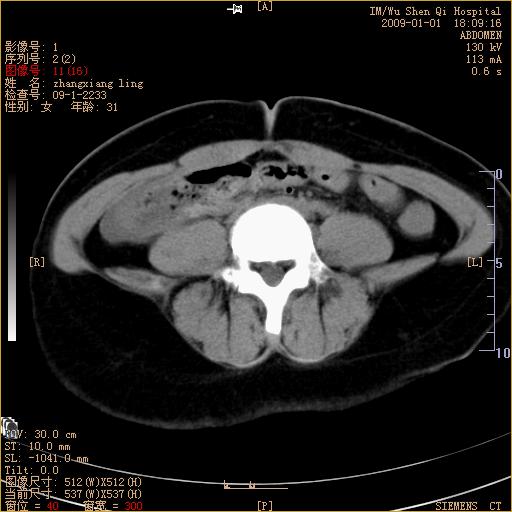

标题: CT17527:F31Y,腹痛伴血便9小时 [打印本页]

标题: CT17527:F31Y,腹痛伴血便9小时

升结肠肠壁不规则增厚,肠腔狭窄,考虑升结肠占位,建议增强扫描

升结肠肠壁不规则增厚,肠腔狭窄,考虑升结肠占位,建议增强扫描,不除外肠套叠.

升结肠肠壁不规则增厚,似呈同心圆改变,其有积液。结合病史首先考虑肠套叠伴肠壁坏死可能性大,结肠肿瘤待排。

患者已手术,结果肠系膜血栓形成肠坏死

结果:患者已手术,结果肠系膜血栓形成肠坏死。回过头再看局部肠壁增厚有分层(高密度坏死及低密度水肿)表现。